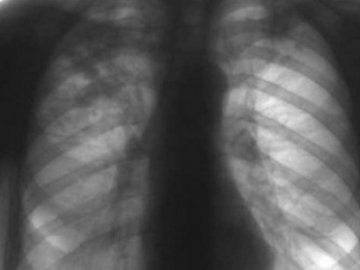

На Волині – нестача лікарів, що працюють з туберкульозниками

На Волині бракує лікарів-фтизіатрів, а 40% лікарів, які працюють із хворими на туберкульоз, – пенсіонери.